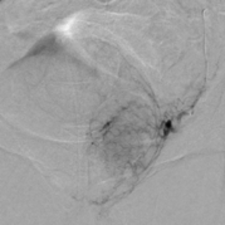

Die Prostataarterienembolisation ist ein schonendes, minimal-invasives Verfahren zur Behandlung einer vergrößerten Prostata (benigne Prostatahyperplasie, BPH).

Dabei werden gezielt kleine Blutgefäße, die die Prostata versorgen, mithilfe winziger Partikel verschlossen. Dadurch schrumpft das Prostatagewebe und die Beschwerden wie häufiges oder erschwertes Wasserlassen lassen nach.

Der Eingriff erfolgt meistens über einen kleinen Zugang in der Leiste und unter örtlicher Betäubung. Für viele Patienten stellt dieses Verfahren eine alternative Behandlungsmöglichkeit dar, vor allem wenn Medikamente nicht mehr ausreichend helfen oder eine Operation vermieden werden soll.